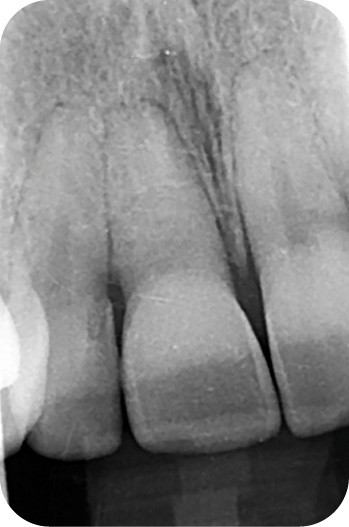

L’éclaircissement dentaire peut être réalisé à domicile (technique ambulatoire) à l’aide de gouttières porte-gel sur mesure fabriquées après prise d’empreinte (fig. 1), ou au cabinet par application de gel après isolation et protection des tissus mous (fig. 2).